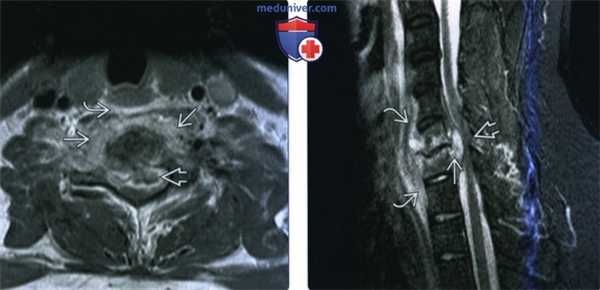

(Слева) На схеме сагиттального среза показан абсцесс шейного отдела спинного мозга, сопровождающийся отеком окружающей паренхимы спинного мозга и увеличением его объема на уровне абсцесса.

(Справа) Сагиттальный срез, Т2-ВИ: образование в центральной части спинного мозга с гиперинтенсивным содержимым и темным контуром, что характерно для воспалительных образований. Отек окружающей паренхимы спинного мозга распространяется краниально до продолговатого мозга и каудально до уровня грудного отдела. Подобная МР-картина не является специфичной для абсцессов, аналогично могут выглядеть первичные и вторичные новообразования спинного мозга. (Слева) Сагиттальный срез, Т2-ВИ, пациент со стрептококковым эндокардитом: диффузное увеличение объема спинного мозга с формированием в его толще на уровне С4-С5-6 кольцевидной зоны с низкоинтенсивной границей (капсула абсцесса).

(Справа) Сагиттальный срез, Т1-ВИ с КУ, пациент со стрептококковым эндокардитом: периферическое контрастное усиление сигнала капсулы абсцесса спинного мозга.